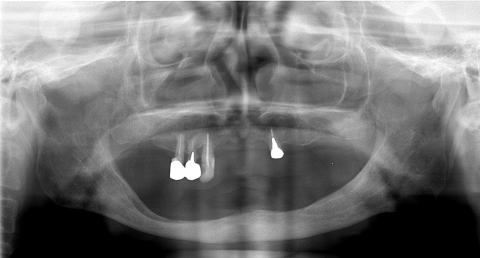

(図6)初診から33年経過(2008年1月7日)、71歳。咬耗は進んでいるが、骨植は堅固である

(図4)32年経過(2007年3月5日)、70歳。十分機能している

(図1)初診時(1975年10月15日)、38歳。歯肉出血が主訴で紹介された。当時、歯周疾患治治療は一部の臨床家以外はあまり関心が払われていなかった

(図2)初診時(1975年10月15日)、38歳。まず徹底的なPlaque Controlから始めた

(図3)初診から2年後(1977年7月)、40歳。Splintせずに機能している